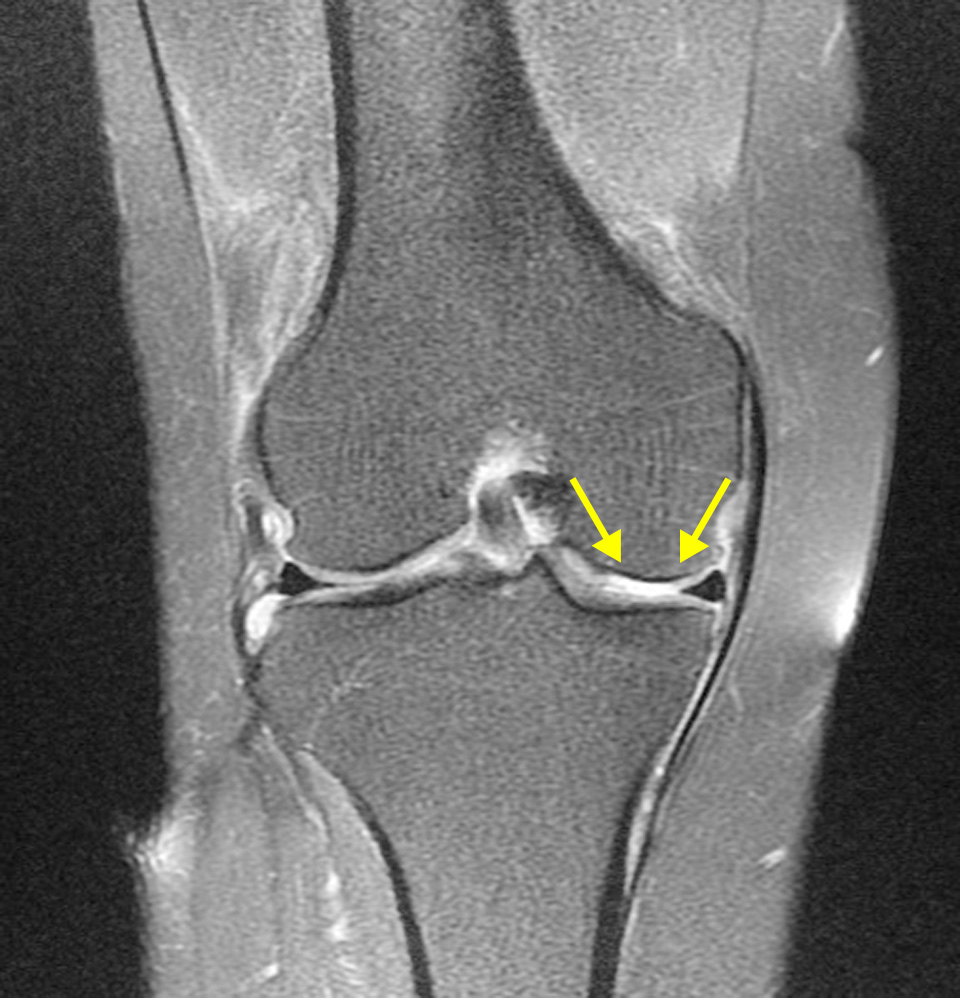

수술전 MRI 에서 외측 반월상 연골판이 파열된 것을 확인할 수 있다.

- 환자 동의하에 게시된 이미지입니다.